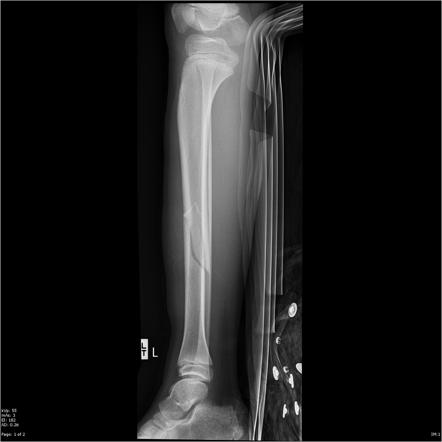

1st stage (fracture repair)

hematoma forms

2nd stage (fracture repair)

soft (fibrocartilaginous) callus forms

3rd stage (fracture repair)

hard (bony) callus forms

4th stage (fracture repair)

remodeling begins

open (compound) fracture

closed (simple) fracture

displaced fracture

transverse fracture

oblique fracture

compression fracture

greenstick fracture

spiral

communiated fracture